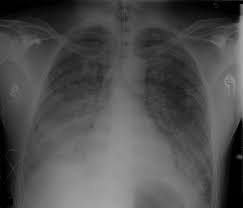

Ards - Formal Guidelines Management Of Acute Respiratory Distress Syndrome Annals Of Intensive Care Full Text : Most people who get ards are already at the hospital for trauma or illness.. Acute respiratory distress syndrome (ards) is a medical condition in which the lungs are not working properly and oxygen blood levels are too low. The american lung association (ala) says ards is a rapidly progressive disease that can occur in critically ill patients—most notably now, in those diagnosed with severe illness resulting from. This month marks the 50th anniversary of the first description of the condition now termed the acute respiratory distress syndrome, or ards. Ards is a type of acute respiratory failure caused by fluid buildup in your lungs. Acute respiratory distress syndrome (ards) occurs when fluid builds up in the tiny, elastic air sacs (alveoli) in your lungs.

Fluid leaks from small blood vessels and collects in tiny. For those who survive, a decreased quality of life is common. Causes may include sepsis, pancreatitis, trauma, pneumonia, and aspiration. Ards is a type of acute respiratory failure caused by fluid buildup in your lungs. But even if they survive, it's a long road to recovery.

This deprives your organs of the oxygen they need to function. On a microscopic level, the disorder is associated with capillary endothelial injury and diffuse alveolar damage. The fluid prevents your lungs from filling with oxygen. Care guide for ards (acute respiratory distress syndrome) (discharge care). The fluid keeps your lungs from filling with enough air, which means less oxygen reaches your bloodstream. Acute respiratory distress syndrome (ards) is a serious lung condition that causes low blood oxygen. People who develop ards often are very ill with another disease or have major injuries. It occurs when fluid fills up the air sacs in your lungs.

On a microscopic level, the disorder is associated with capillary endothelial injury and diffuse alveolar damage. Most people who get ards are already at the hospital for trauma or illness. The outcomes tend to be better in younger patients, trauma patients and when ards is caused by blood transfusions. Acute respiratory distress syndrome (ards) is a condition that causes fluid to build up in your lungs so oxygen can't get to your organs. The american lung association (ala) says ards is a rapidly progressive disease that can occur in critically ill patients—most notably now, in those diagnosed with severe illness resulting from. Most people who develop ards are in the hospital for other serious health problems. In ards, fluid builds up inside the tiny air sacs of the lungs, and surfactant breaks down. The condition causes fluid to accumulate in the lungs, which in turn reduces blood oxygen to dangerously low levels. The diagnosis of ards is based on fulfilling three criteria: Care guide for ards (acute respiratory distress syndrome) (discharge care). People who develop ards are usually ill due to another disease or a major injury. Possible causes, signs and symptoms, standard treatment options and means of care and support. Ards is a medical emergency.

Ards, or acute respiratory distress syndrome, is a lung condition that leads to low oxygen levels in the blood. Covid‐19 ards is a predictable serious complication of covid‐19 that requires early recognition and comprehensive management this disease is still too strange to us, and there are too many doubts, says dr ling qin (lq), after reviewing more than 400 patients with coronavirus disease 2019 (covid‐19) pneumonia in wuhan union hospital, china. In ards, fluid builds up inside the tiny air sacs of the lungs, and surfactant breaks down. Acute respiratory distress syndrome (ards) is a form of acute lung injury and occurs as a result of a severe pulmonary injury that causes alveolar damage heterogeneously throughout the lung. Most people who get ards are already at the hospital for trauma or illness. Causes may include sepsis, pancreatitis, trauma, pneumonia, and aspiration. Ards is a type of acute respiratory failure caused by fluid buildup in your lungs. Acute respiratory distress syndrome (ards) is a medical condition in which the lungs are not working properly and oxygen blood levels are too low.

Acute respiratory distress syndrome, or ards, is an inflammatory lung injury that happens when fluids build up in small air sacs (called alveoli) in the lungs. Causes may include sepsis, pancreatitis, trauma, pneumonia, and aspiration. This lecture will cover ards pathophysiolo. It occurs when fluid fills up the air sacs in your lungs. Acute respiratory distress syndrome (ards) occurs when fluid builds up in the tiny, elastic air sacs (alveoli) in your lungs. Acute respiratory distress syndrome (ards) is a severe lung condition. Care guide for ards (acute respiratory distress syndrome) (discharge care). This month marks the 50th anniversary of the first description of the condition now termed the acute respiratory distress syndrome, or ards. The outcomes tend to be better in younger patients, trauma patients and when ards is caused by blood transfusions. Acute respiratory distress syndrome affects 200,00 people in the us each year. People who develop ards are usually ill due to another disease or a major injury. The american lung association (ala) says ards is a rapidly progressive disease that can occur in critically ill patients—most notably now, in those diagnosed with severe illness resulting from. On a microscopic level, the disorder is associated with capillary endothelial injury and diffuse alveolar damage.

The acute respiratory distress syndrome (ards) is a common cause of respiratory failure in critically ill patients and is defined by the acute onset of noncardiogenic pulmonary oedema, hypoxaemia and the need for mechanical ventilation. The fluid prevents your lungs from filling with oxygen. In ards, fluid builds up inside the tiny air sacs of the lungs, and surfactant breaks down. People who develop ards are usually ill due to another disease or a major injury. Ards is a medical emergency. Acute respiratory distress syndrome, or ards, is an inflammatory lung injury that happens when fluids build up in small air sacs (called alveoli) in the lungs. Possible causes, signs and symptoms, standard treatment options and means of care and support. Acute respiratory distress syndrome (ards) is a condition that causes fluid to build up in your lungs so oxygen can't get to your organs.

This month marks the 50th anniversary of the first description of the condition now termed the acute respiratory distress syndrome, or ards. Breathing becomes difficult and oxygen cannot get into the body. In ards, fluid builds up inside the tiny air sacs of the lungs, and surfactant breaks down. Acute respiratory distress syndrome (ards) is a condition that causes fluid to build up in your lungs so oxygen can't get to your organs. Acute respiratory distress syndrome (ards) is a form of acute lung injury and occurs as a result of a severe pulmonary injury that causes alveolar damage heterogeneously throughout the lung. The condition leads to a buildup of fluid in the air sacs which prevents enough oxygen from passing into the bloodstream. The authors of this review discuss our current understan. Ards is a medical emergency. Acute respiratory distress syndrome (ards) is a serious lung condition that causes low blood oxygen. Too much fluid in your lungs can lower the amount of oxygen or. For those who survive, a decreased quality of life is common. Ards progresses through several phases after a direct pulmonary or indirect extrapulmonary insult. The diagnosis of ards is based on fulfilling three criteria: